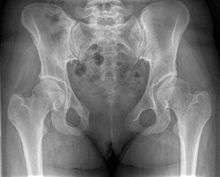

Diastasis symphysis pubis is the separation of normally joined pubic bones, as in the dislocation of the bones, without a fracture.

X-ray

An X-ray film will show a marked gap between the pubic bones, normally there is a 4–5 mm gap but in pregnancy, hormonal influences cause relaxation of the connecting ligaments and the bones separate up to 9 mm. To demonstrate instability of the joint the patient is required to stand in the "flamingo" position, (standing with weight on one leg and the other bent).[1] A vertical displacement of more than 1 cm is an indicator of symphysis pubis instability.[2] A displacement of more than 2 cm usually indicates involvement of the sacroiliac joints.